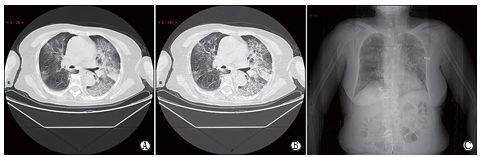

图6 超早期CT影像

A. 女性,33岁,职业暴露,斑片状磨玻璃密度影;B. 男性,67岁,与患者有过接触史,大片磨玻璃密度影;C. 女性,35岁,职 业暴露,大片实变影、内见充气支气管征

图7 早期CT影像

男性,38岁,无明显诱因发热(39.3℃)、干咳和气短3d。实 验室检查,WBC:3.01×109/L(减低),LYMPH:0.81×109/L(减 低),CRP:60.8 mg/L(升高),PCT:0.16 ng/ml(增高)。影像学检查示双肺多发片团影较淡实变及网格样增厚小叶间隔。

图8 快速进展期CT影像

女性,50岁,纳差、乏力、肌肉酸痛、鼻塞流涕1周、咽痛咽痒2d。实验室检查,WBC:4.08×109/L(正常)、LYMPH:0.96×109/L (减低)、CRP:60.8 mg/L(升高)、ESR:25 mm/h(升高)。影像学检查,双肺多发片团影较淡实变及网格样增厚小叶间隔。